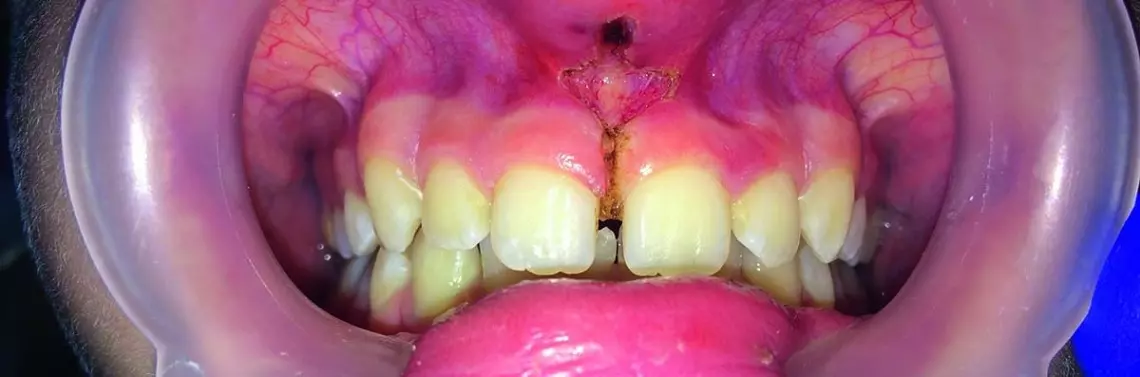

Typy brodawkowy i penetrujący (III, IV) są uważane za nieprawidłowe. Typy III i IV wędzidełka wargi górnej doprowadzają do powstania diastemy prawdziwej i wynikającej z niej zaburzeń fonacji i estetyki, gromadzenia biofilmu, chorób periodontologicznych, jak również zmniejszenia ilości zrogowaciałego nabłonka dziąsła. W wielu przypadkach przerost wędzidełka może ograniczać ruch wargi, zaburzać mimikę twarzy lub powodować brak utrzymania uzupełnień protetycznych.

Test Blancha

W celu zakwalifikowania przerośniętego wędzidełka do leczenia można posłużyć się testem Blancha. Jest on dodatni, jeśli przy pociągnięciu wargi górnej do góry i do przodu dochodzi do anemizacji błony śluzowej podniebiennej i międzyzębowej okolicy 11 i 21.

Opis przypadku

Przed wykonaniem zabiegu końcówkę światłowodu należy aktywować (nadpalić) poprzez jej dwu- lub trzykrotne przyłożenie do kalki zgryzowej podczas pracy lasera diodowego. Po znieczuleniu pacjenta niedużą ilością środka znieczulającego (ok. 0,5 ml) rozpoczyna się wycinanie wędzidełka poprzez przyłożenie końcówki aktywnego światłowodu do tkanki. Rozróżnia się wiele technik operacyjnych, takich jak plastyka V, Y i Z. Celem zabiegu jest usunięcie przyczepu wędzidełka do poziomu okostnej. Dokładna technika zabiegu jest przedstawiona w dokumentacji wideo. Ranę po działaniu lasera przemywa się solą fizjologiczną i pokrywa preparatami Periokin lub Solcoseryl. Po zabiegu nie ma konieczności stosowania szycia. Proponowane ustawienia mocy lasera są uzależnione od zawartości hemoglobiny w tkance. Zaleca się ustawienie początkowe mocy lasera na 1,5 W w trybie pracy ciągłej i podwyższenie mocy do poziomu maksymalnie 2,5 W, aby zwiększyć skuteczność odparowania (cięcia) tkanki.